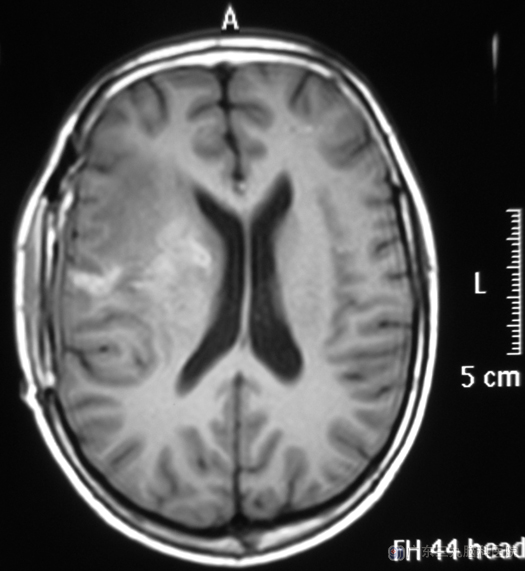

小徐一天前出现头部钝痛,疼痛部位不固定,难以忍受,不能缓解,伴有呕吐数次。家人担心脑袋了长了肿瘤。立即送他去当地医院检查,头颅CT检查提示右侧额叶、基底节区巨大占位性病变,广东三九脑科医院头颅MR检查:右侧基底节区示一囊状占位性病变,大小约为62.4mm×44.9mm×45.0mm,中线结构向左偏,考虑脑脓肿可能性大。

由鲁主任主刀,在唤醒麻醉下行右侧额叶、基底节区脑脓肿壁部分切除术,术中导航定位,显微镜下见脓肿壁与脑组织粘连严重,分离困难,切开脓肿腔,吸引器吸除残余脓液,冲洗脓肿腔,沿脓肿壁分离分块切除,过程顺利。术后病理:脑脓肿。